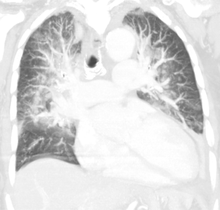

Low oxygen saturation and disturbed arterial blood gas readings support the proposed diagnosis by suggesting a pulmonary shunt. Chest X-ray will show fluid in the alveolar walls, Kerley B lines, increased vascular shadowing in a classical batwing peri-hilum pattern, upper lobe diversion (increased blood flow to the superior parts of the lung), and possibly pleural effusions. In contrast, patchy alveolar infiltrates are more typically associated with noncardiogenic edema[2]

Lung ultrasound, employed by a healthcare provider at the point of care, is also a useful tool to diagnose pulmonary edema; not only is it accurate, but it may quantify the degree of lung water, track changes over time, and differentiate between cardiogenic and non-cardiogenic edema.[15]